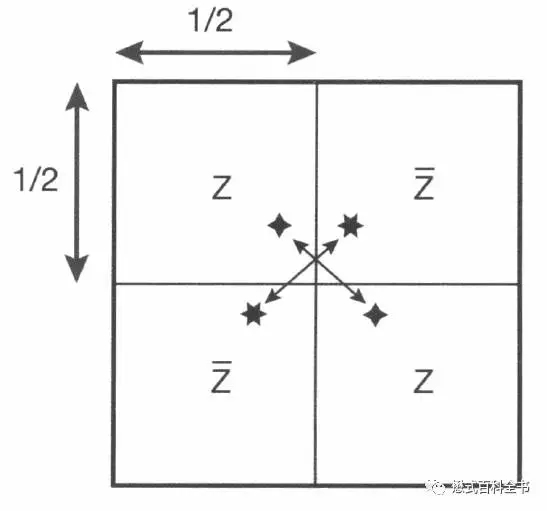

图6:K空间的共轭对称示意图

这里什么叫共轭对称呢?共轭对称的意思是:当一个函数,它的实部为偶函数,虚部为奇函数的时候,并且满足f(x)=f(-x),这个函数就叫共轭对称函数。简单的说就是,把K空间分为四个象限的话,每个对角线都是对称的。

图7-8:K空间共轭对称示意图。